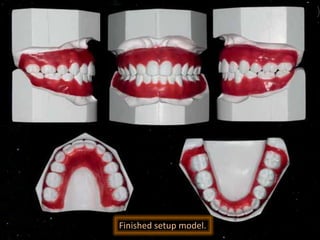

Finished setup model.

Finished treatment showing the treatment objectives were achieved